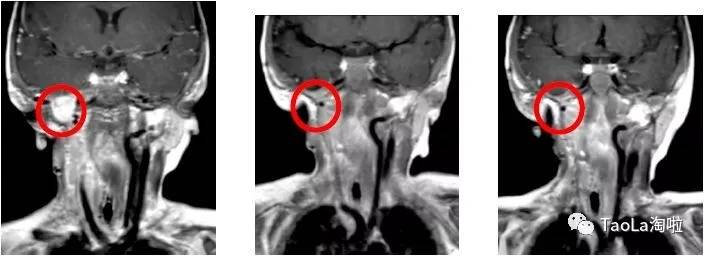

儿童纤维肉瘤:

16个月大的的婴儿

治疗前:经过基因检测后发现ETV6-NTRK3突变,接受了3次手术和化疗,效果依然不明显。

治疗后:接受抗癌药Vitrakvi成人剂量的液体制剂治疗3周期后,MRI磁共振显示肿瘤体积减少90%!